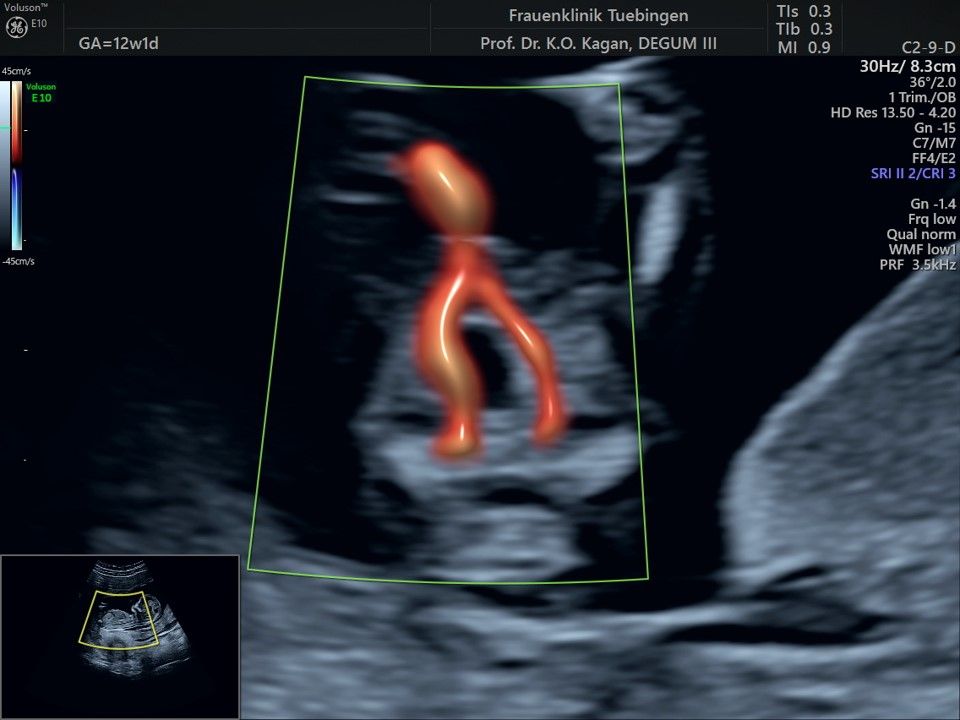

Herz

Das Ergebnis der Ultraschalluntersuchung ist wegweisend. Dabei wird der Fet vermessen, die Organe werden untersucht und die sonographischen Marker zur Risikoberechnung für Chromosomenstörungen werden beurteilt. Das sind: die Nackentransparenzdicke, Nasenbein sowie der Blutfluss in der rechten Herzhälfte und im Ductus venosus, einem Gefäß in der Leber des Feten.